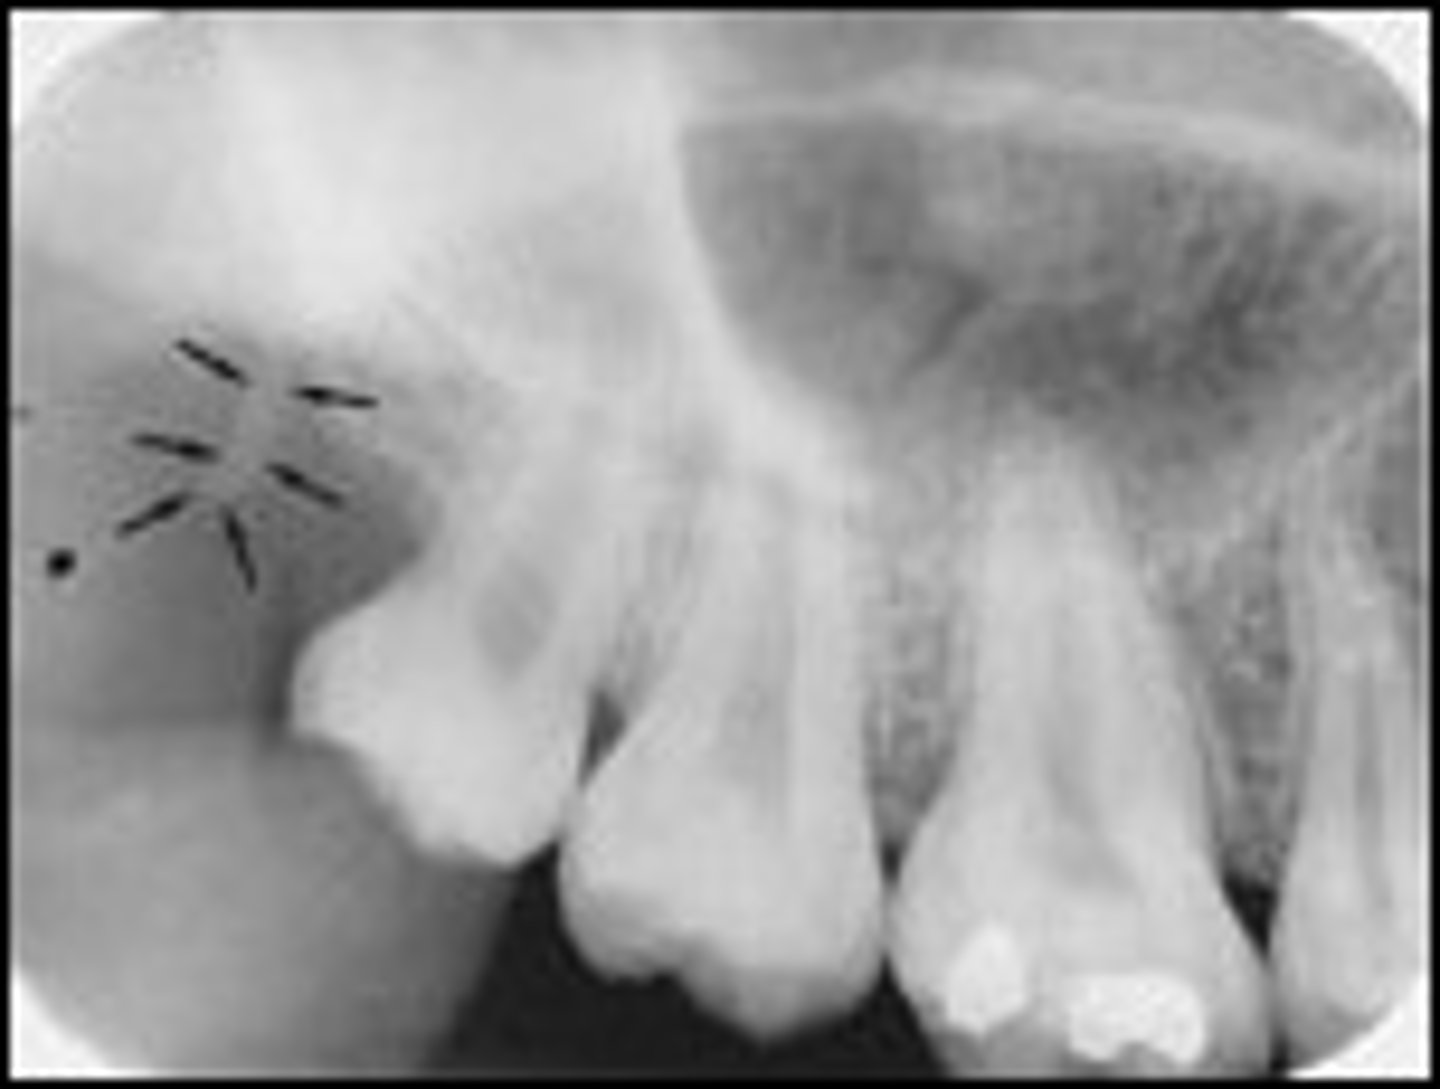

what is this?

what is this radiolucent area in the image?